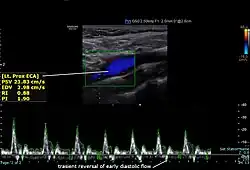

Diagnostics

The condition and health of the external carotid arteries is usually evaluated using Doppler ultrasound, CT angiogram or phase contrast magnetic resonance imaging (PC-MRI). Typically, blood flow velocities in the external carotid artery are measured as peak systolic velocity (PSV) and end diastolic velocity (EDV).[4]

PSV values greater than 200 cm/s are considered to be predictive of more than 50% of external carotid artery stenosis.[5]